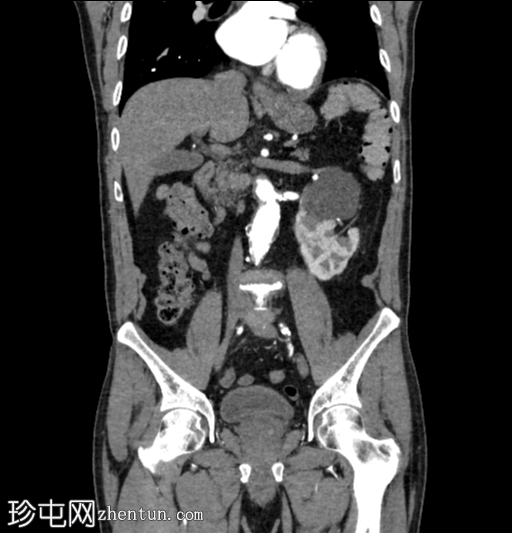

冠状位增强扫描

动脉期

右向左交叉融合性肾异位(轴位、冠状位和矢状位图像),右侧异位肾上极与左侧肾下极融合。

肾皮质囊肿。

主动脉-髂动脉粥样硬化晚期改变。

本病例展示了交叉融合性肾异位,其发生率高于非融合型肾异位。

评估相关并发症(例如肾结石)至关重要。